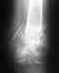

Перелом локтевого отростка, МОС 28.11.19. Снят гипс 27.12.19. Не разрабатывается рука. В чем причина, непонятно.

Угол сгибания локтя примерно 110-150 гр., с момента снятия гипса прогресса практически нет (ЛФК ежедневно,несколько раз в день). Встал вопрос, возможно, рука больше и не согнется пока пластина внутри? Или же, нужно просто больше времени? Буду очень благодарна за ответы